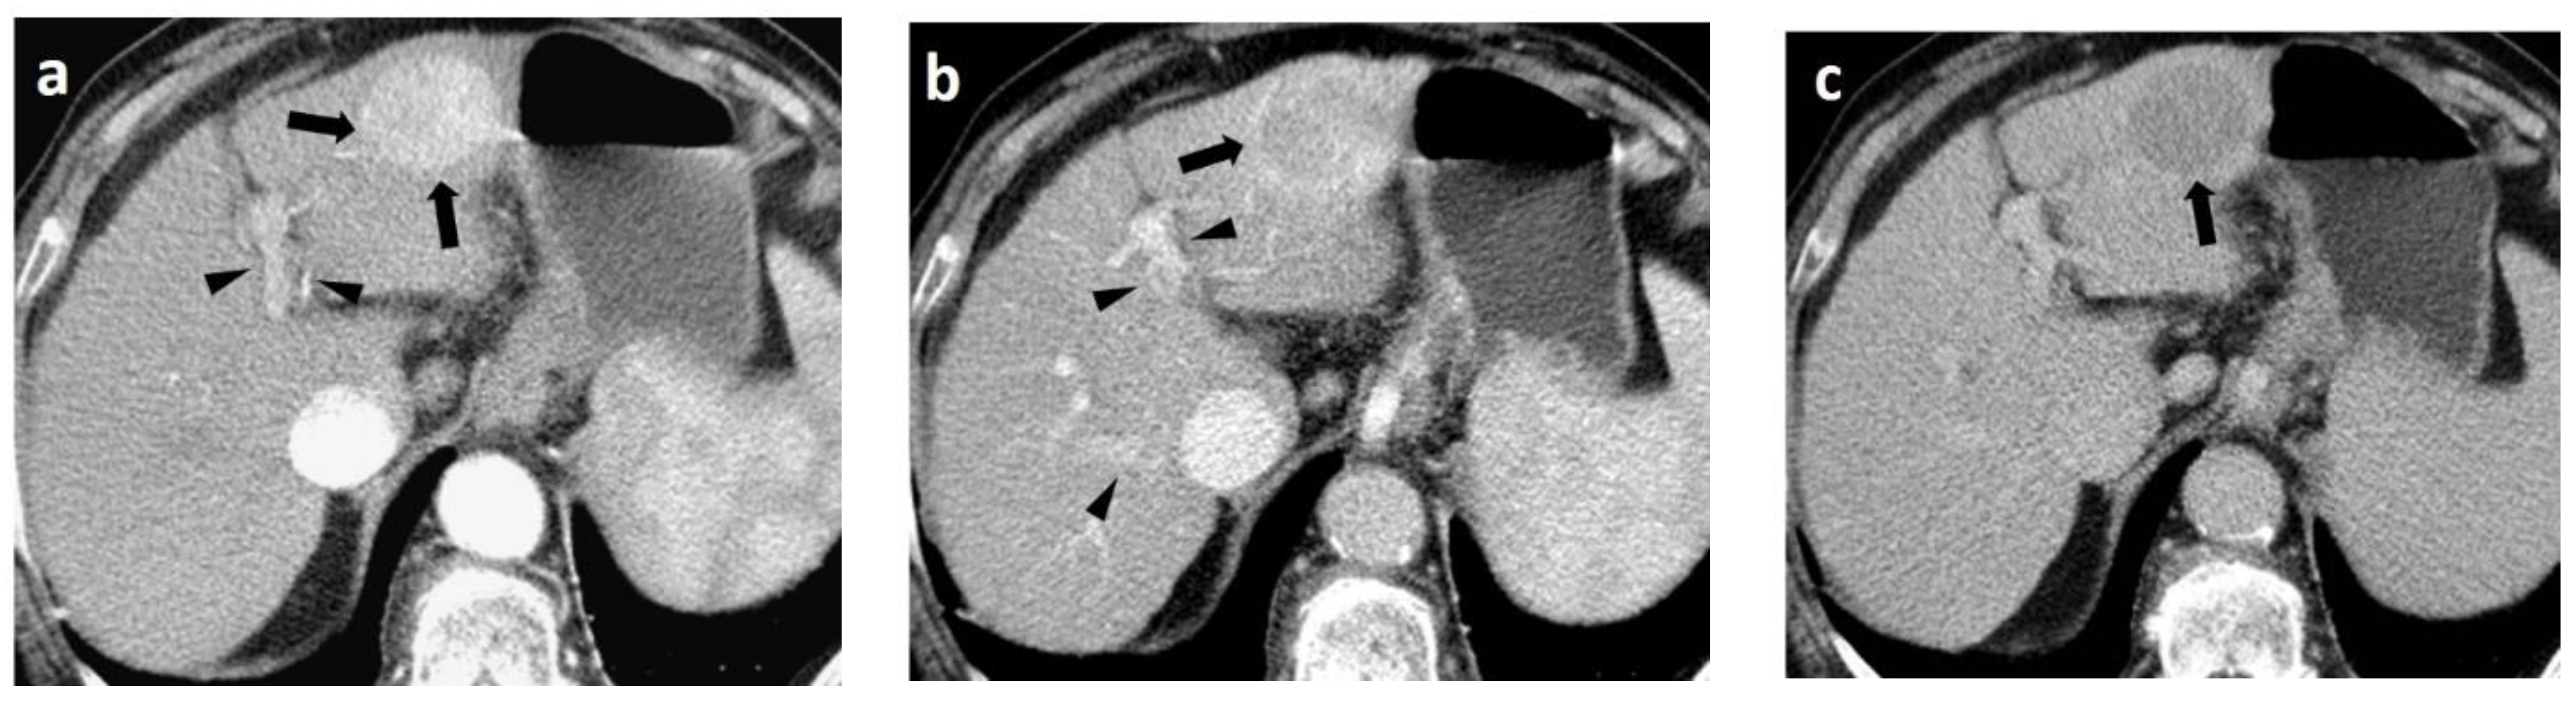

4. CT

- Choi, J.-Y.; Lee, J.-M.; Sirlin, C.B. CT and MR Imaging Diagnosis and Staging of Hepatocellular Carcinoma: Part I. Development, Growth, and Spread: Key Pathologic and Imaging Aspects. Radiology 2014, 272, 635–654. [Google Scholar] [CrossRef]

- Lee, J.H.; Lee, J.M.; Kim, S.J.; Baek, J.H.; Yun, S.H.; Kim, K.W.; Han, J.K.; Choi, B.I. Enhancement patterns of hepatocellular carcinomas on multiphasic multidetector row CT: Comparison with pathological differentiation. Br. J. Radiol. 2012, 85, e573–e583. [Google Scholar] [CrossRef]

- Zhu, F.; Yang, F.; Li, J.; Chen, W.; Yang, W. Incomplete tumor capsule on preoperative imaging reveals microvascular invasion in hepatocellular carcinoma: A systematic review and meta-analysis. Abdom. Radiol. 2019, 44, 3049–3057. [Google Scholar] [CrossRef]